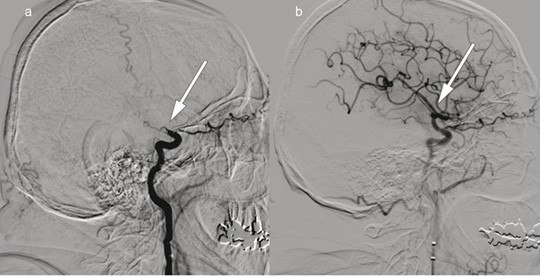

Patient 2. A woman in her 70s experienced acute onset of right-sided paralysis, dizziness and dysarthria after heart surgery. Her NIHSS score was 23 points (severe cerebral infarction). Intravenous thrombolytic therapy was contraindicated. The image to the right shows cerebral angiography with contrast injection in the left vertebral artery, c) before and d) after embolectomy of a large thrombus (arrows) with occlusion of the superior cerebellar artery, posterior cerebral artery and the bifurcation of the basilar artery. Embolectomy was performed with recanalisation 220 minutes after symptom onset. The event presumably occurred after heart surgery. Further workup also revealed atrial fibrillation. The patient received anticoagulation therapy with warfarin, and at follow-up three months later, the NIHSS score was 0 points.